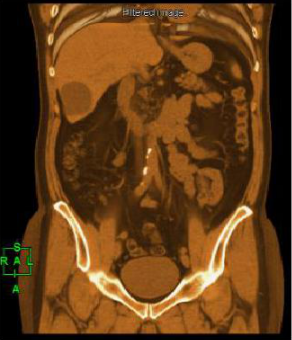

在整體的影像鏈環節進行了改進确保高清晰的圖像。實現了圖像的各向同性,任意方向的 MPR 圖像具有相同的圖像質量。